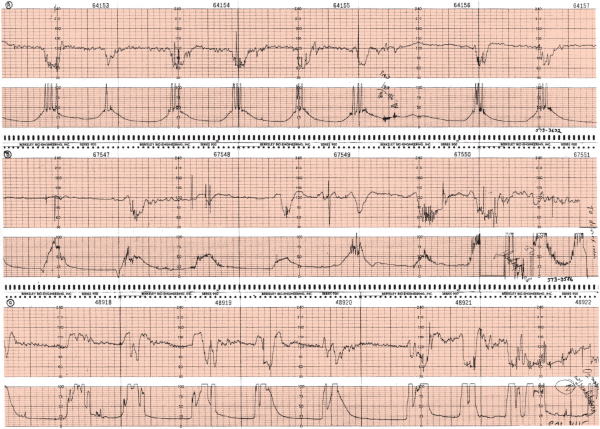

aceler.png

brad.png

des prec.png

des tard.png

des var.png

fcf_norm.png

taq.png

variabilidad.jpg

variabilidad_reducida.jpg